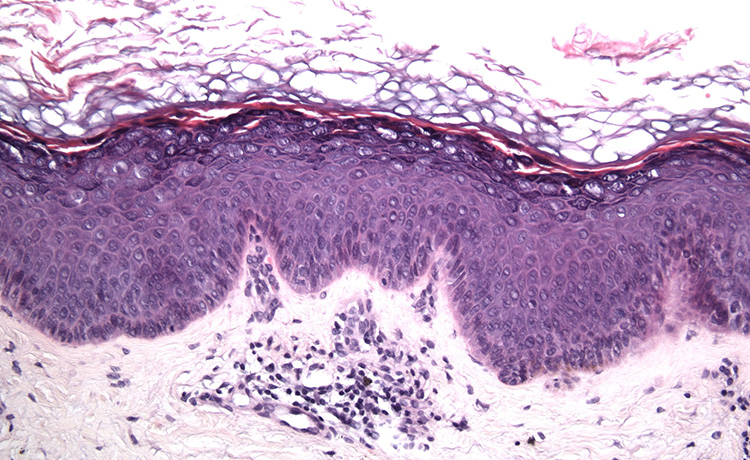

Cilt kanserini, deri üzerinde oluşan malignant (kötücül) büyümeler olarak açıklamak mümkündür. Cilt kanserleri birçok farklı türe ayrılır. Bunlar; Melanom cilt kanseri, Bazal Hücreli Karsinom, Skuamöz Hücreli Karsinom ve Kaposi Sarkomu gibi hem yapısal hem patolojik olarak birbirinden farklı kanser türleridir. Ancak bu kanser türleri arasında en çok korkulan ve ölümcül kanser türlerinden biri olarak kabul edileni, melanom cilt kanseridir. Melanom kanseri, deriye rengini veren ‘’melanin’’ isimli renk pigmentlerini oluşturan melanosit hücrelerinin anormal bir şekilde büyüyerek çoğalması ile oluşan kanser türüdür.

Deride bulunan sağlıklı melanosit hücrelerin çeşitli faktörler ile mutasyona uğrayarak çoğalması sonucunda deri üzerinde lekeler ortaya çıkar. Kanser hücresinden kaynaklı oluşan bu lekeler, çoğu zaman normal bir ben ile benzerlik gösterebilmektedir. Vücutta herhangi bir uyarı vermeden ortaya çıkan benler, daha önceden var olan benlerin üzerinde de gelişebilir. Cilt kanserinin en önemli belirtileri arasında deri üzerinde ortaya çıkan bu cilt lekeleri yer alır. Cilt lekelerinin kanser hücresi olup olmadığını anlamak için, normal benler ile cilt kanserinin neden olduğu benlerin farklarının anlaşılması gerekir.

Cilt üzerindeki renk ve doku değişikliği, lekelerin çapı ve şişliği doktor tarafından incelenir. Bu inceleme sırasında Dermatoskopi adı verilen ve ciltteki lekeleri 10-20 kat kadar büyütebilen alet ile benler incelenebilir. Elle tutulabilen Dermatoskopi aleti ile benlerin görüntü kaydı alınır. Bu yöntem normal benler ile kanserli hücrelerin ayrımında önemli bir rol oynar. Ancak cilt kanserinin kesin tanısının konulabilmesi için patolojik inceleme yapılması gerekir. Bunun için ciltte oluşan bene biyopsi uygulanır. Biyopsi sonrasında hastanın cilt kanseri olup olmadığı kesinleştirilir.